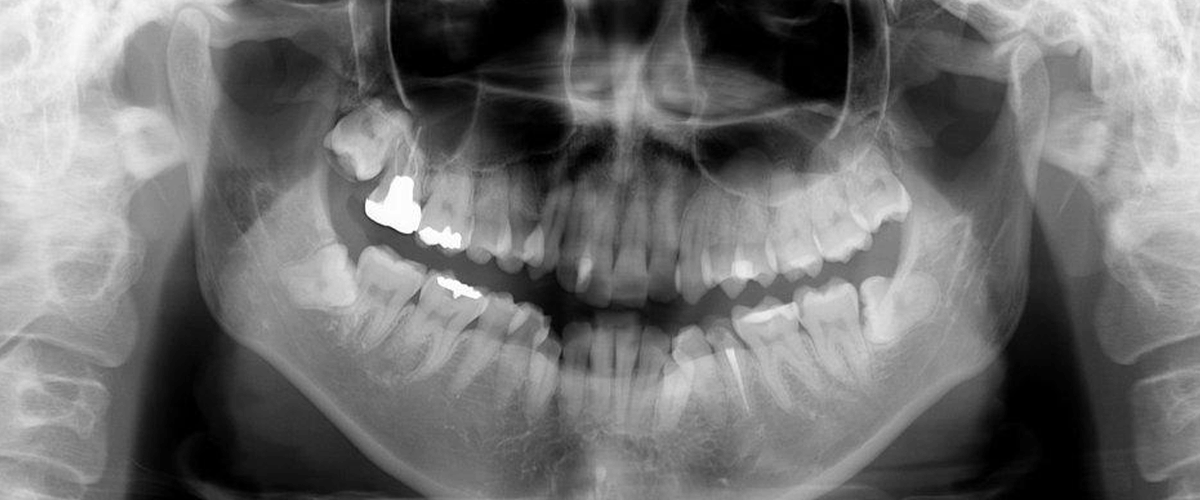

顎の骨は人により形態が異なり、その内部には数多くの神経や血管が通い、従来のレントゲン写真では骨の影になった神経や血管を確認することができません。三次元の高画質画像が得られる歯科用CTを用いることで、見えなかった部分を確認することができ、さらに治療診断の精度を上げることができるようになります。

- 今まで見えなかった歯の中や、骨の中まで立体的に見ることができます。

- インプラント治療だけでなく歯周病・根管治療・親知らずの抜歯などすべての歯科治療において、治療の精密さや安全性がさらに向上します。